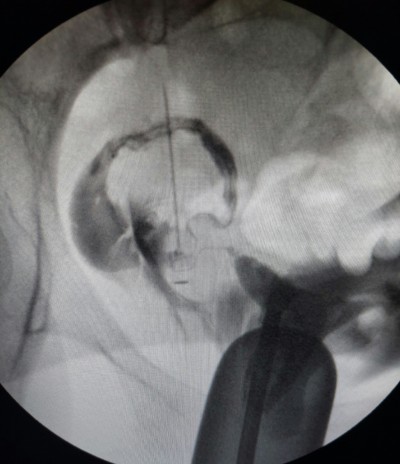

Hsg sonucunda sol iyi, sağ bölümde odem var ama o tupte açık. Bu durumu yaşayan oldu mi geçen sene 4 aylıkken kaybettim bir daha da hamile kalamadım.